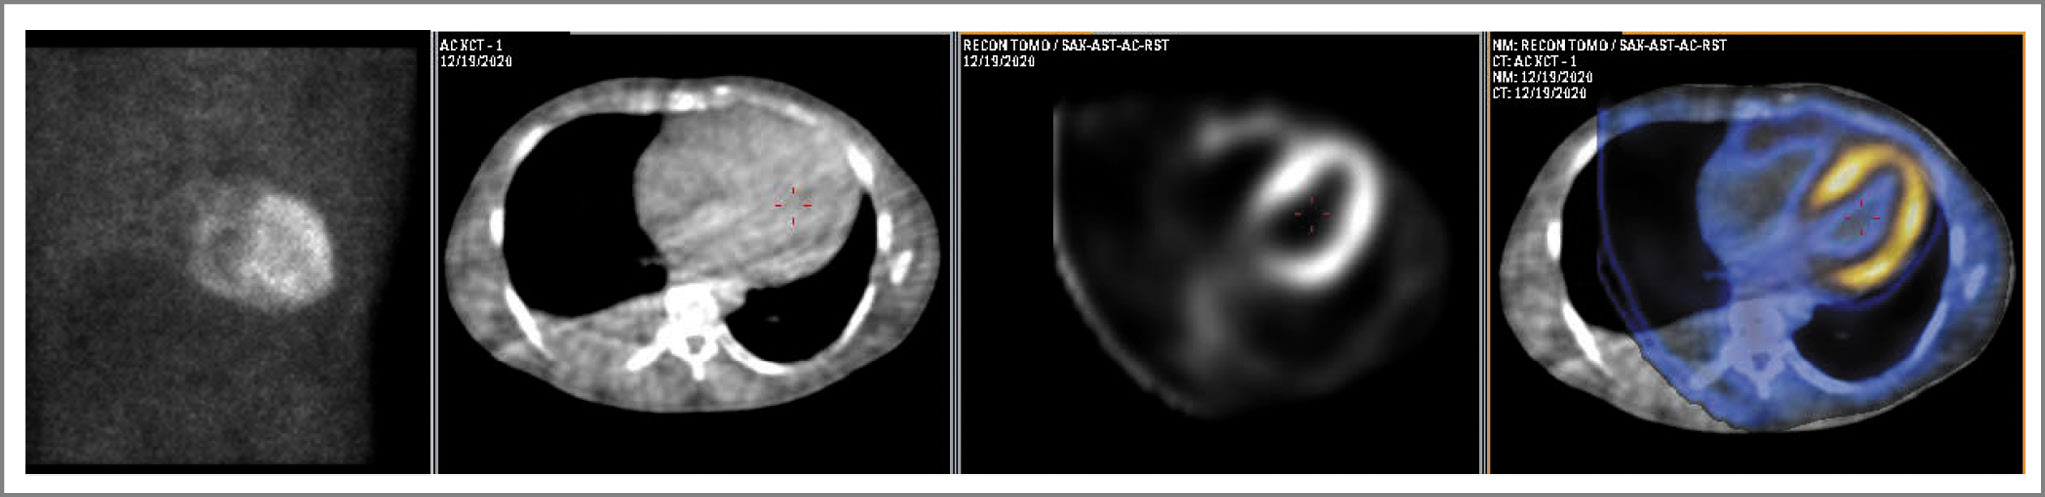

Клинический пример

В качестве иллюстрации приводим итоги наблюдения за пациентом К., возраст 81 год, с ХСН II функционального класса (ФК) по NYHA, асимметричной гипертрофией ЛЖ, фракцией выброса (ФВ) ЛЖ 49%. При проведении сцинтиграфии костей скелета в другом учреждении с целью онкопоиска было отмечено накопление 99mTc-PYP в области сердца. Значение H/Cl, измеренное по полученным изображениям, превышало 1,5, в результате чего пациенту поставлен диагноз: «TTR-амилоидоз». В рамках госпитализации пациента в ФГБУ «НМИЦ кардиологии им. акад. Е.И. Чазова» с целью подбора медикаментозной терапии установленного заболевания по данным комплексной ЭхоКГ характерных признаков амилоидоза сердца не выявлено, по данным МРТ – признаки некомпактного миокарда. В отделе радионуклидной диагностики и позитронно-эмиссионной томографии ФГБУ «НМИЦ кардиологии им. акад. Е.И. Чазова» пациенту повторно проведена сцинтиграфия миокарда с 99mTc-PYP по приведенному выше протоколу. При планарной сцинтиграфии, выполненной через 1 ч, отмечалось значительное накопление РФП в проекции сердца (H/Cl=1,37), однако по данным ОЭКТ/КТ на фоне интенсивной циркуляции РФП в полостях сердца накопление РФП в миокарде отсутствовало (Grade 0; рис. 3).

Рис. 3. Данные планарной сцинтиграфии, КТ, ОЭКТ и ОЭКТ/КТ пациента К. При планарном исследовании отмечается накопление РФП в проекции сердца, однако по данным ОЭКТ/КТ это накопление относится к полостям желудочков и предсердий (сигнал от пула крови); включения РФП в миокард не выявляется. / Fig. 3. Data of planar scintigraphy, CT, SPECT and SPECT/CT of patient K. In planar examination, accumulation of radiopharmaceuticals in the projection of the heart is noted, however, according to SPECT/CT data, this accumulation refers to the cavities of the ventricle and atria (signal from the blood pool); the inclusion of radiopharmaceuticals in the myocardium is not detected.

Таким образом, диагноз амилоидоза у пациента был исключен, а результат первого сцинтиграфического исследования признан ложноположительным вследствие ошибочного суждения только лишь по планарным изображениям, выполненным не в прицельном режиме и без набора достаточной статистики счета, что привело к большой погрешности при вычислении H/Cl.